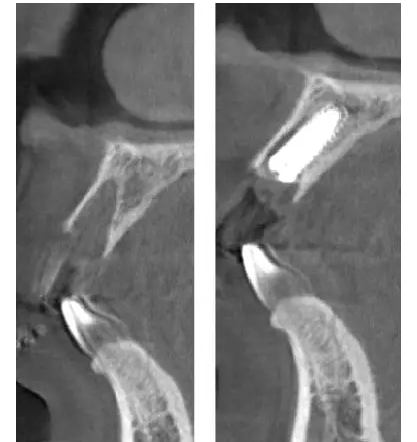

術前、術后CT

在口腔種植領域中,由于各種原因造成的種植牙局部牙槽突骨量不足或種植體周圍骨缺損的修復在種植外科的研究中已經取得了重大突破。新一代的血漿提取物--濃縮生長因子(CGF,Concentrate Growth Factors)能夠明顯縮短術區成骨的時間,提高成骨質量,促進成骨及組織的愈合;具體有:引導骨再生技術、聯合骨膜表面覆蓋加速軟組織愈合、用于上頜竇提升、拔牙后即刻種植、牙槽嵴位點保存、頜骨囊腫的治療、牙槽骨修整。